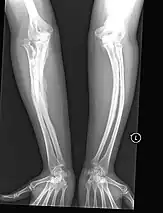

The main symptom of osteogenesis imperfecta is fragile, low mineral density bones; all types of OI have some bone involvement.[5] In moderate and especially severe OI, the long bones may be bowed, sometimes extremely so.[28] The weakness of the bones causes them to fracture easily—a study at the Endocrine Unit at the National Institute of Child Health in Karachi, Pakistan found an average of 5.8 fractures per year in untreated children.[29] Fractures typically occur much less after puberty, but begin to increase again in women after menopause and in men between the ages of 60 and 80.[1]: 486

- Type V – Having the same clinical features as type IV, it can be clinically distinguished by observing a "mesh-like" appearance to a bone biopsy under a microscope. Type V can be further distinguished from other types of OI by the "V triad": an opaque band (visible on X-ray) adjacent to the growth plates; hypertrophic calluses (abnormally large masses of bony repair tissue) which form at fracture sites during the healing process; and calcification of the interosseous membrane of the forearm,[50] which may make it difficult to turn the wrist.[1]: 429 Other features of this condition may include pulled elbow, and, as in other types of OI, long bone bowing and hearing loss.[64] Cases of this type are caused by mutations in the IFITM5 gene on chromosome 11p15.5.[64][49] The separation of type V from type IV OI, its clinical type, was initially suggested even before its genetic cause was known, by Glorieux et al. in 2000.[50][65] Type V is relatively common compared to other genetically defined types of OI—4% of OI patients at the genetics department of the Brazilian Hospital de Clínicas de Porto Alegre were found to have it.[66]